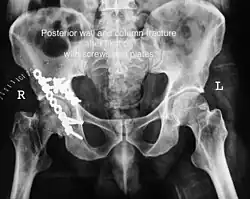

Elementary fractures

-

Posterior wall fracture as seen on 3-D CT scan -

Posterior wall fracture fixed with screws and plate -